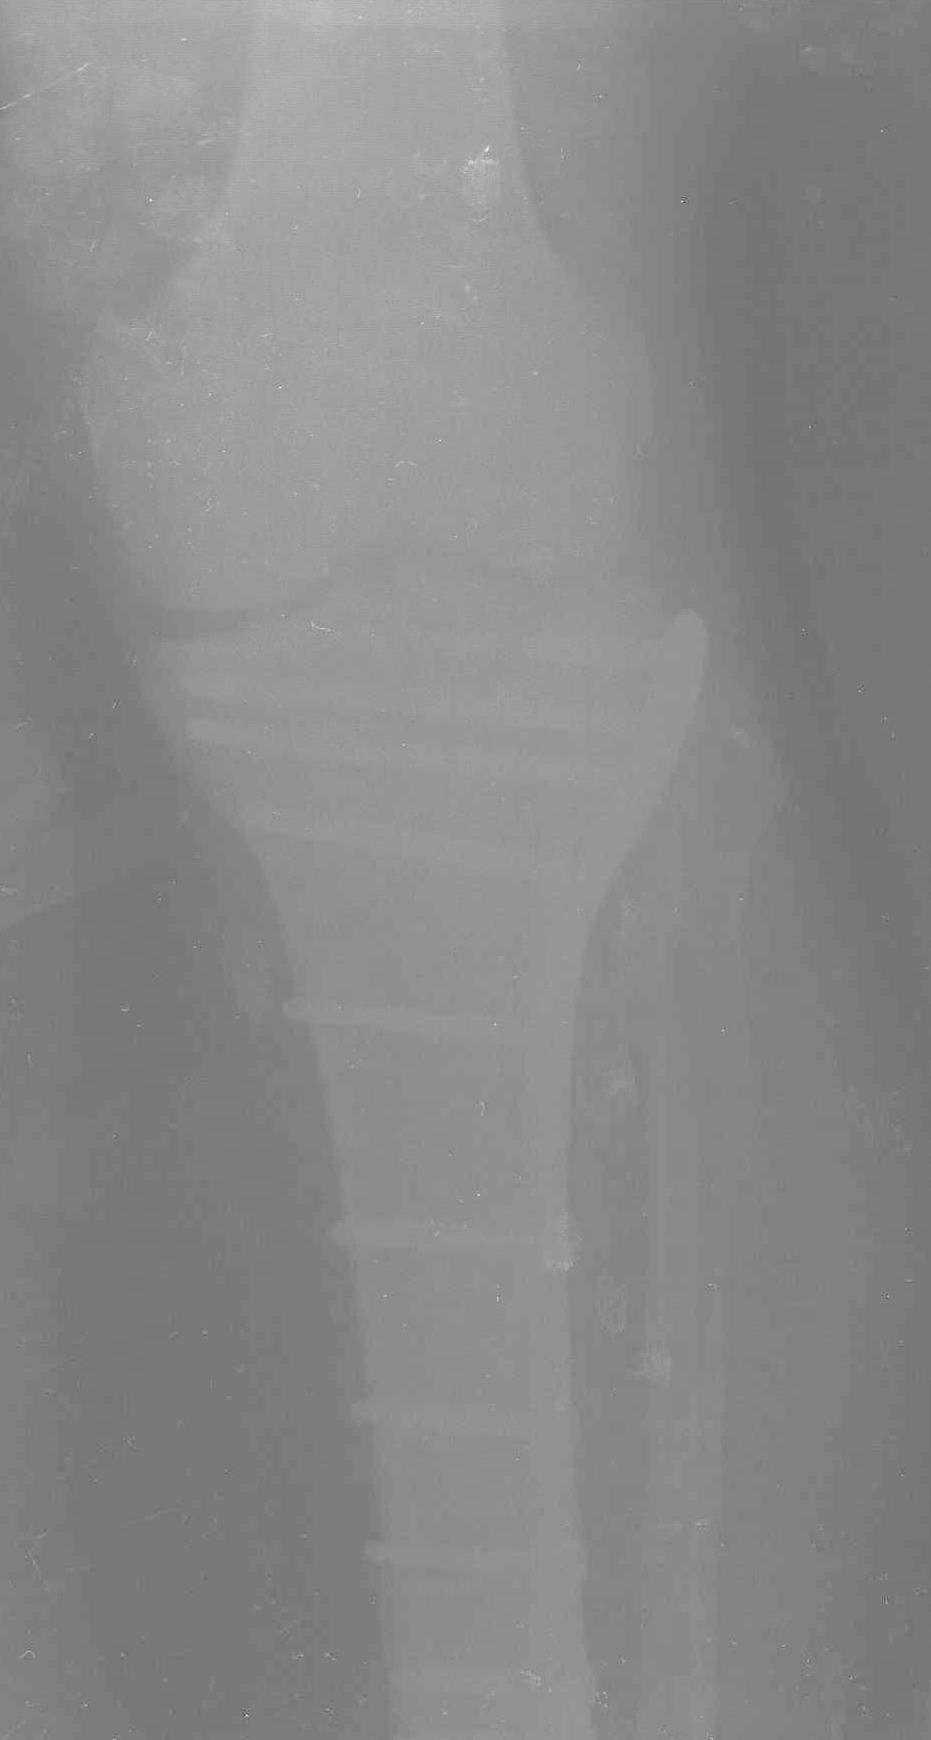

Трудно поверить, что разрекламированная Ортопедическая школа Восточной Украины позволяет такие странные снимки? На прямом снимке сохранен общий контур плато, но не известна судьба импрессии суставной поверхности. На полубоковой?, оставлен без репозиции задне-медиальный отдел, и навряд ли после такой фиксации можно удовлетвориться результатом.

Такая ситуация характерна для многих, когда принимается ошибочное решение, т.е пытаются фиксировать одним имплантом переломы двух мыщелков. Латеральная пластина приемлема только для тех случаев, когда сохраняется интактным медиальный диафизарный кортекс и отсутствует фрагментация на верхушке медиального перелома.

Представленные снимки не информативны, нужны отдельные качественные снимки коленного сустава и голени без ротации.